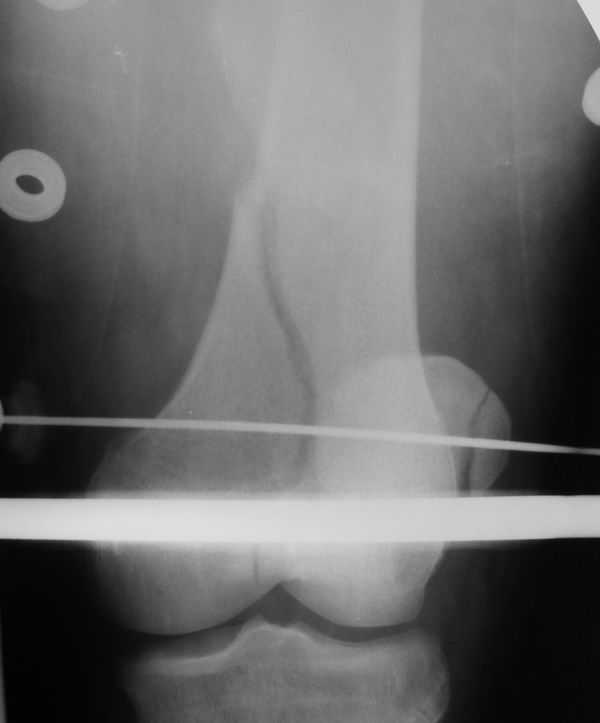

Уважаемые коллеги! Поступил пациент 46 лет после автоаварии от 3.01.

Лечился в ЦРБ. К нам поступил вчера. Имеется оскольчатый перелом диафиза

левого бедра, перелом медиального мыщелка, краевой перелом надколенника.

У нас, кроме того, выявили перелом шейки бедра. Перелом закрытый,

имеется рана в в/3 голени(ниже уровня бугристости б/берцовой кости)без

признаков инфицирования.